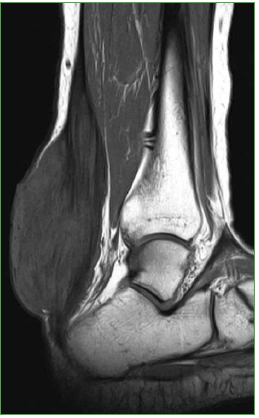

La RM de tobillos muestra engrosamiento difuso de aspecto fusiforme de ambos tendones de Aquiles. El tendón adquiere un patrón de señal heterogéneo reticulado, con señal iso-hiperintensa en secuencias de T1 y densidad protónica con supresión grasa interpuesta entre las fibras tendinosas normales hipointensas. De manera incidental, en el estudio de los tobillos, se encontró un similar patrón de presentación por RM, en ambos tendones peroneos largos (Figuras 3 y 4).

Figura 3.

Resonancia magnética, corte axial potenciado en densidad protónica con supresión grasa (3990/36) del tendón de Aquiles izquierdo. Además del engrosamiento, esta proyección permite ver el patrón reticular característico de la entidad presentada. Similar hallazgo se repite en el tendón peroneo largo (puntas de flechas).

Figura 4.

Resonancia magnética, corte sagital potenciado en T1 (660/25) del tendón de Aquiles izquierdo. Se advierte un marcado engrosamiento fusiforme del tendón de Aquiles con señal heterogénea a expensas de hiperintensidad global que alterna con trabeculaciones lineales que reflejarían tejido patológico (probablemente con cambios inflamatorios asociados) y fascículos residuales de colágeno normal, respectivamente.